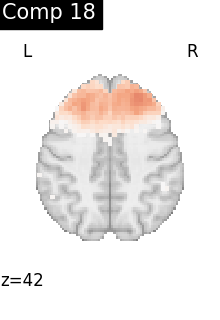

One plot of each component

for i, cur_img in enumerate(iter_img(dictlearning_components_img)):

plot_stat_map(

cur_img,

display_mode="z",

title=f"Comp {int(i)}",

cut_coords=1,

vmax=0.1,

vmin=-0.1,

colorbar=False,

)